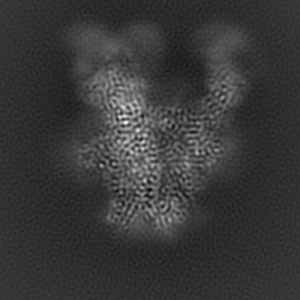

Cryo-EM structure of ConSOSL.UFO.664 (ConS) in complex with bNAb PGT122

Single-particle3.12 Å

Sample: ConSOSL.UFO.664 in complex with bNAb PGT122

Fitted models: 7lx2